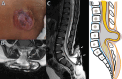

Background Spinal dysraphisms refer to the congenital abnormalities of the spine and spinal cord due to aberrations in the processes of gastrulation, primary neurulation, and secondary neurulation. Embryology of many complex spinal dysraphisms are yet poorly understood and there is no agreeable anatomical-clinicoradiological classification with inclusion of recently documented and complex spinal dysraphisms. Aims and Objectives The main objective of this study was to review the imaging features of spinal dysraphisms with a better understanding of embryological abnormalities and propose a new classification inclusive of all complex and unusual dysraphisms based on anatomical and clinicoradiological correlation. Materials and Methods This was a retrospective single institutional observational study of 391 cases of spinal dysraphism for 10 years in our institution. Of 391 cases included in the study, 204 were males and 187 were females. Also, 123 cases belonged to the 0-6 months age group, 38 cases belonged to the 7-12 months age group, 156 belonged to the 1-5 years age group, 39 cases belonged to the 6-10 years age group, and 35 cases belonged to 10-20 years age group. Results An anatomical-clinicoradiological analysis of cases yielded a high proportion of cases of spinal lipomas, including lipomyeloceles and lipomyelomeningoceles (31.3%) and posterior myelomeningocele (14.2%). Anterior myelocoele (0.2%), sacral chordoma(0.2%), and intrasacral meningocele (0.2%) formed the least proportion of cases. A new classification was proposed based on the analysis of acquired data. Conclusion A structured approach in imaging spinal dysraphism is necessary for imaging evaluation in recent years. The proposed new classification based on clinicoradiological correlation and anatomic location is inclusive of unusual and complex dysraphisms.